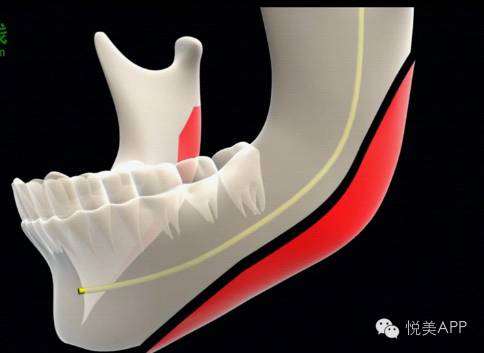

下面要讲的是目前国内下颌骨整形手术的三条截骨线,我们标一下——

很多人只是简单的完成了最简单的1号线——去掉肥大的下颌角,但是却形成了个二求货——两个下颌角——2号线也是一样的,只是角往前了

所以现在一些技术高超,经验丰富的专家,都转而选择三号线——超长的一条截骨线,一直要截到下巴颏结节的位置,尽可能的让它做到角度变大以外的流畅、对称,让脸彻底的瘦下来,而且更好的保护我们的下齿槽神经管。

关于超长结骨线,我放在后面写,感兴趣的同学等下哈